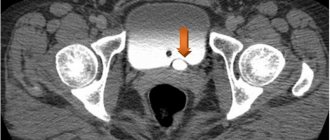

Problems with the genitourinary system can cause great harm to the entire body. Ureterocele disease in women